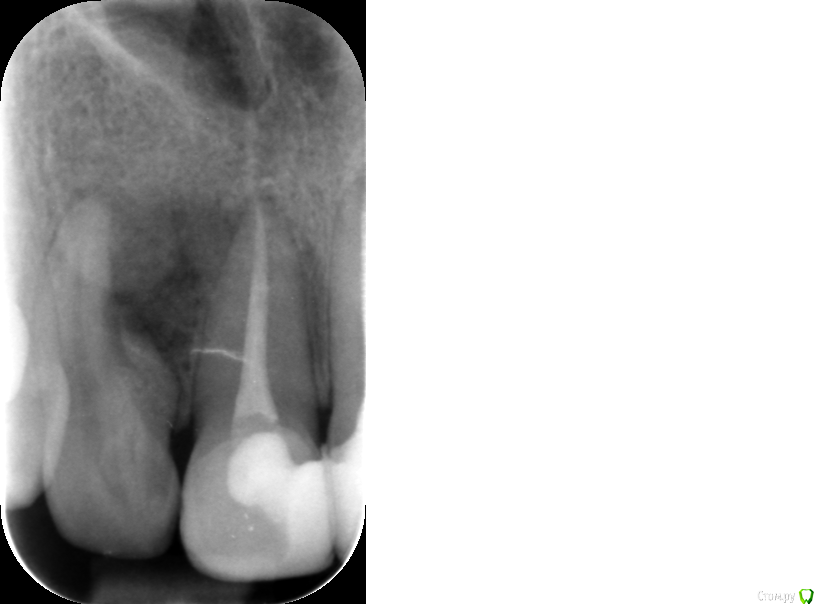

olga1985 Опубликовано 17 сентября, 2016 Автор Поделиться Опубликовано 17 сентября, 2016 добавляю снимки на сегодняшний день. врач сравнил снимки апреля и сентября. сказал, что на 21 зубе не нужно было убирать материал вышедший за корень потому что не это было причиной боли, а боковой канал. но сказал, что сейчас ничего делать не нужно, пока наблюдать. а на проблемный 21 решил, что скорее всего будет достаточно пломбирования. если нет, то будет вкрывать десну и отрезать кусок этого загнутого корня, как мне и советовал первый врач на форуме. Ссылка на комментарий

olga1985 Опубликовано 6 октября, 2016 Автор Поделиться Опубликовано 6 октября, 2016 запломбировали каналы, снимок прикрепляю 2 Ссылка на комментарий